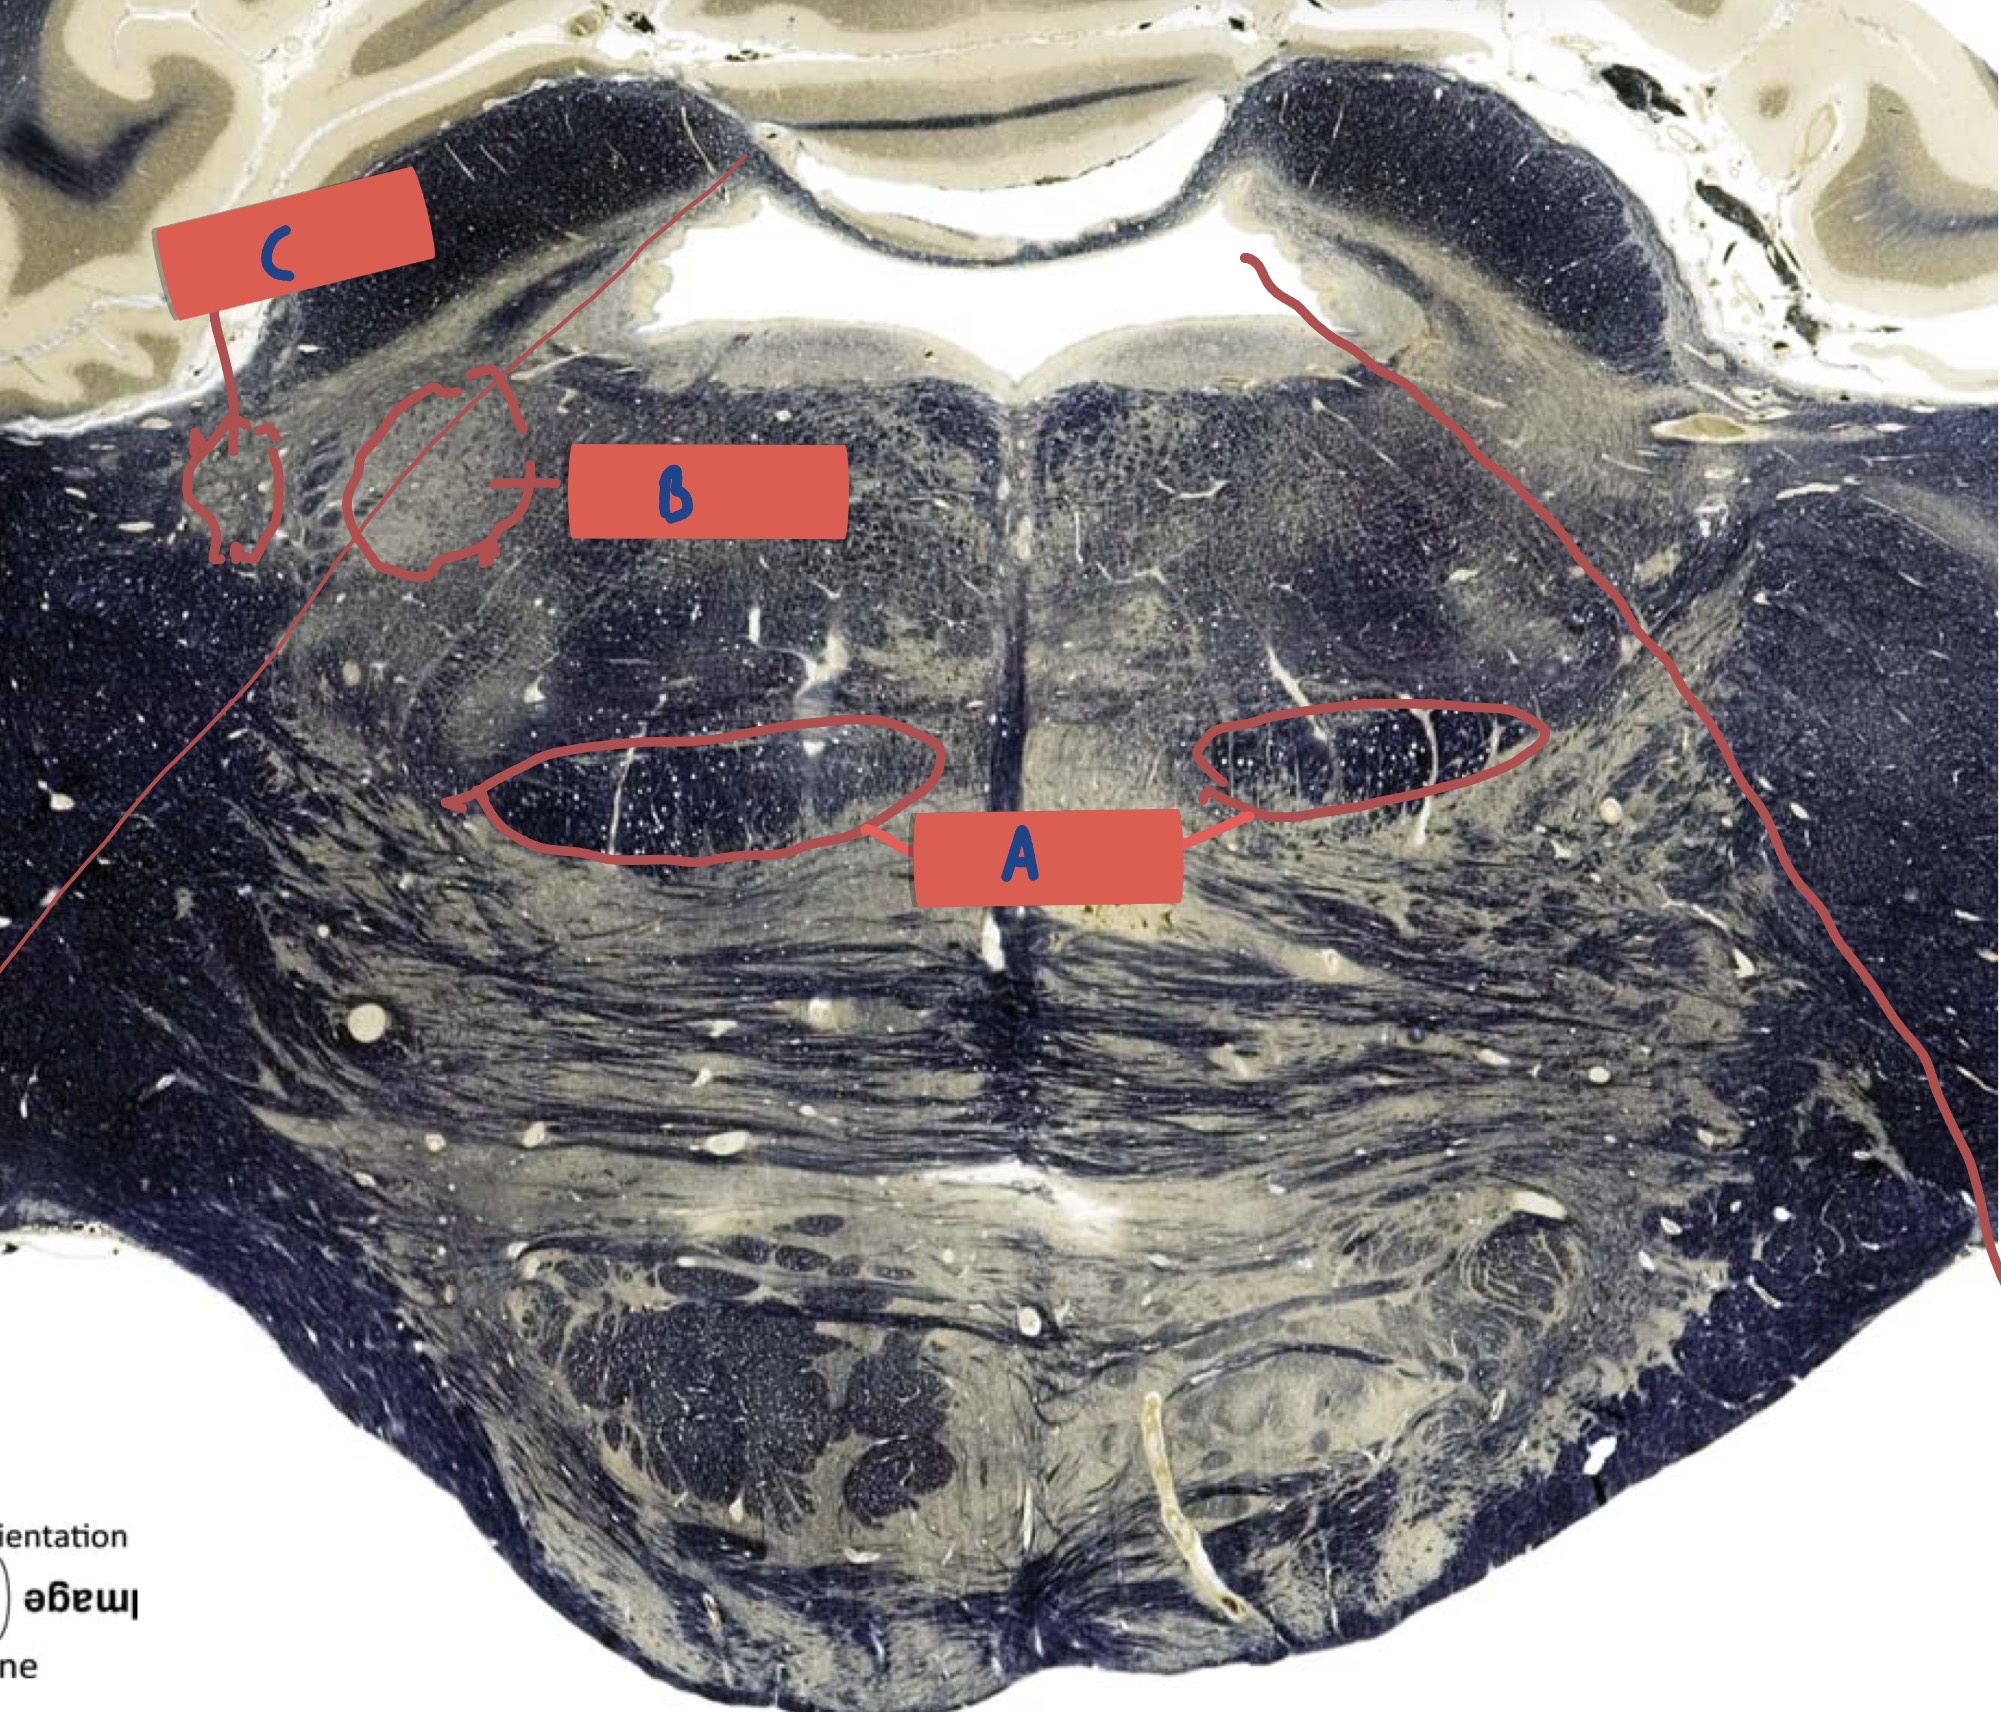

What is A?

Gracile fasticulus

What is B?

Cuneate fasciculus

What is C?

Spinal trigeminal tract

What is D?

Internal Arcuate Fibre

What is E?

Principle olivary nucleus

What is F?

Medial lemniscus